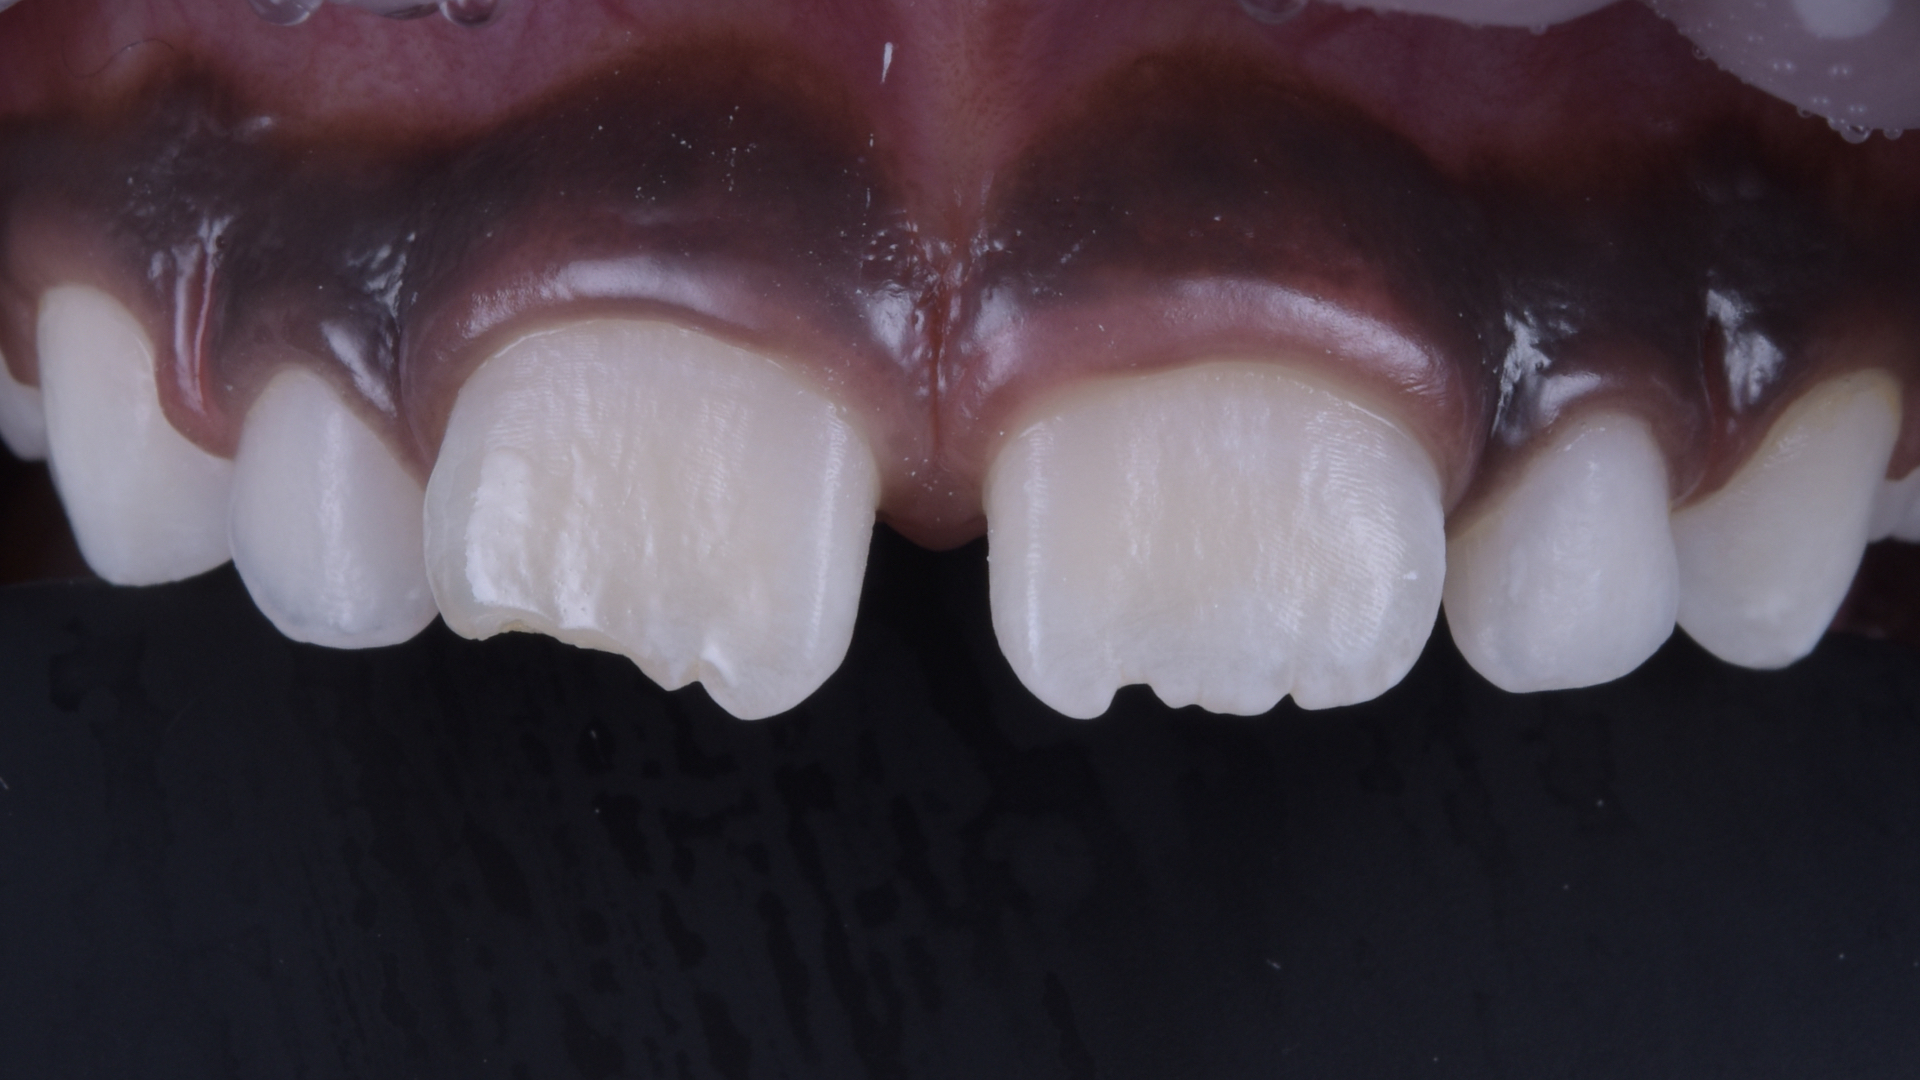

Restauration nach Fertigstellung.

Eine komplette Produktbeschreibung entnehmen Sie bitte der Gebrauchsanweisung (IFU). Ergebnisse können abweichen.